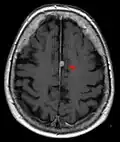

T1 (note CSF is dark) with contrast (arrow pointing to meningioma of the falx)

T1 (note CSF is dark) with contrast (arrow pointing to meningioma of the falx) -